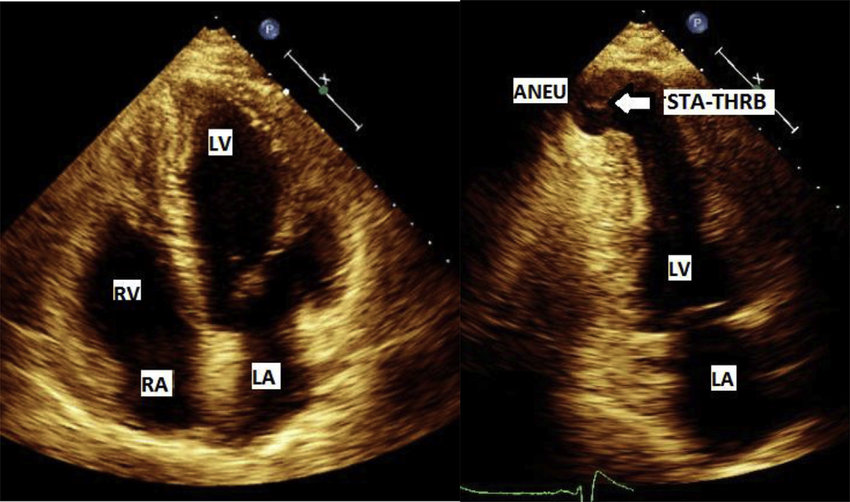

True cardiac aneurysm

What is seen in the 2D image?

Pseudoaneurysm

True aneurysm

Localized, full-thickness bulge of the heart wall that is still intact, but weakened.

Surrounded by myocardial tissue.

A saccular outpouching with a narrow neck originating from a discontinuity in the heart wall.

Narrow neck and lack myocardial or endocardial tissue.